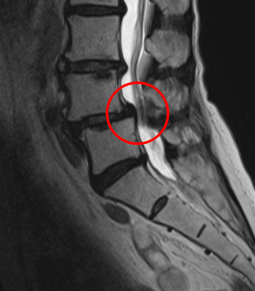

治療前

┃検査・診断

MRI画像を確認したところ、赤い枠で囲った箇所(L4/5)に脊柱管狭窄症の症状が認められ、かなり強く狭窄してしまっていました。腰痛や、左下肢の痛み、痺れの原因はこの狭窄だと判断しました。